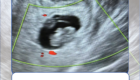

• Siêu âm sản phụ khoa, chẩn đoán dị tật thai nhi sớm;

Một số hình ảnh các hoạt động tại Khoa Sản: